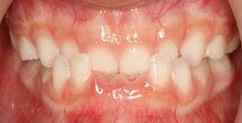

4、開咬(前歯を閉じることができない)

・乳歯列期から治療を開始することを推奨します。

歯の位置は、唇や頬の筋肉(外側からの力)と舌の圧力(内側からの力)のバランスによって決まります。つまり、どこかに発育不全の部分があると、この正常なバランスが崩れて不正咬合を引き起こしてしまうのです。

最近は特に、口をいつもあけている(口呼吸)子どもたちが非常に多くなってきていますが、口呼吸でたえず口を開けていると、舌を正しい位置に収めることができなかったり、唇まわりや頬の筋肉などを正常な状態で使えなかったりして、口周りの筋肉のバランスが崩れてしまいます。

その結果、開咬になり、口呼吸がもっとひどくなる可能性がありますので早い段階での軌道修正をおススメします。